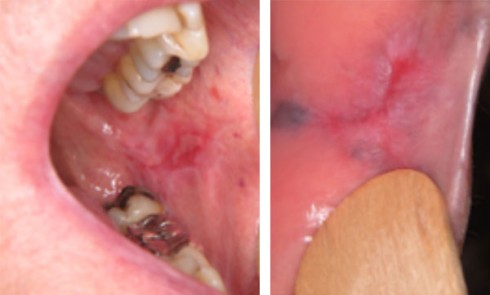

Article réservé à nos abonnés Et si ce n’était pas un lichen ?

Cas 1     Motif de la consultation. Patient de 51 ans venu consulter pour des douleurs jugales gauches. Histoire...